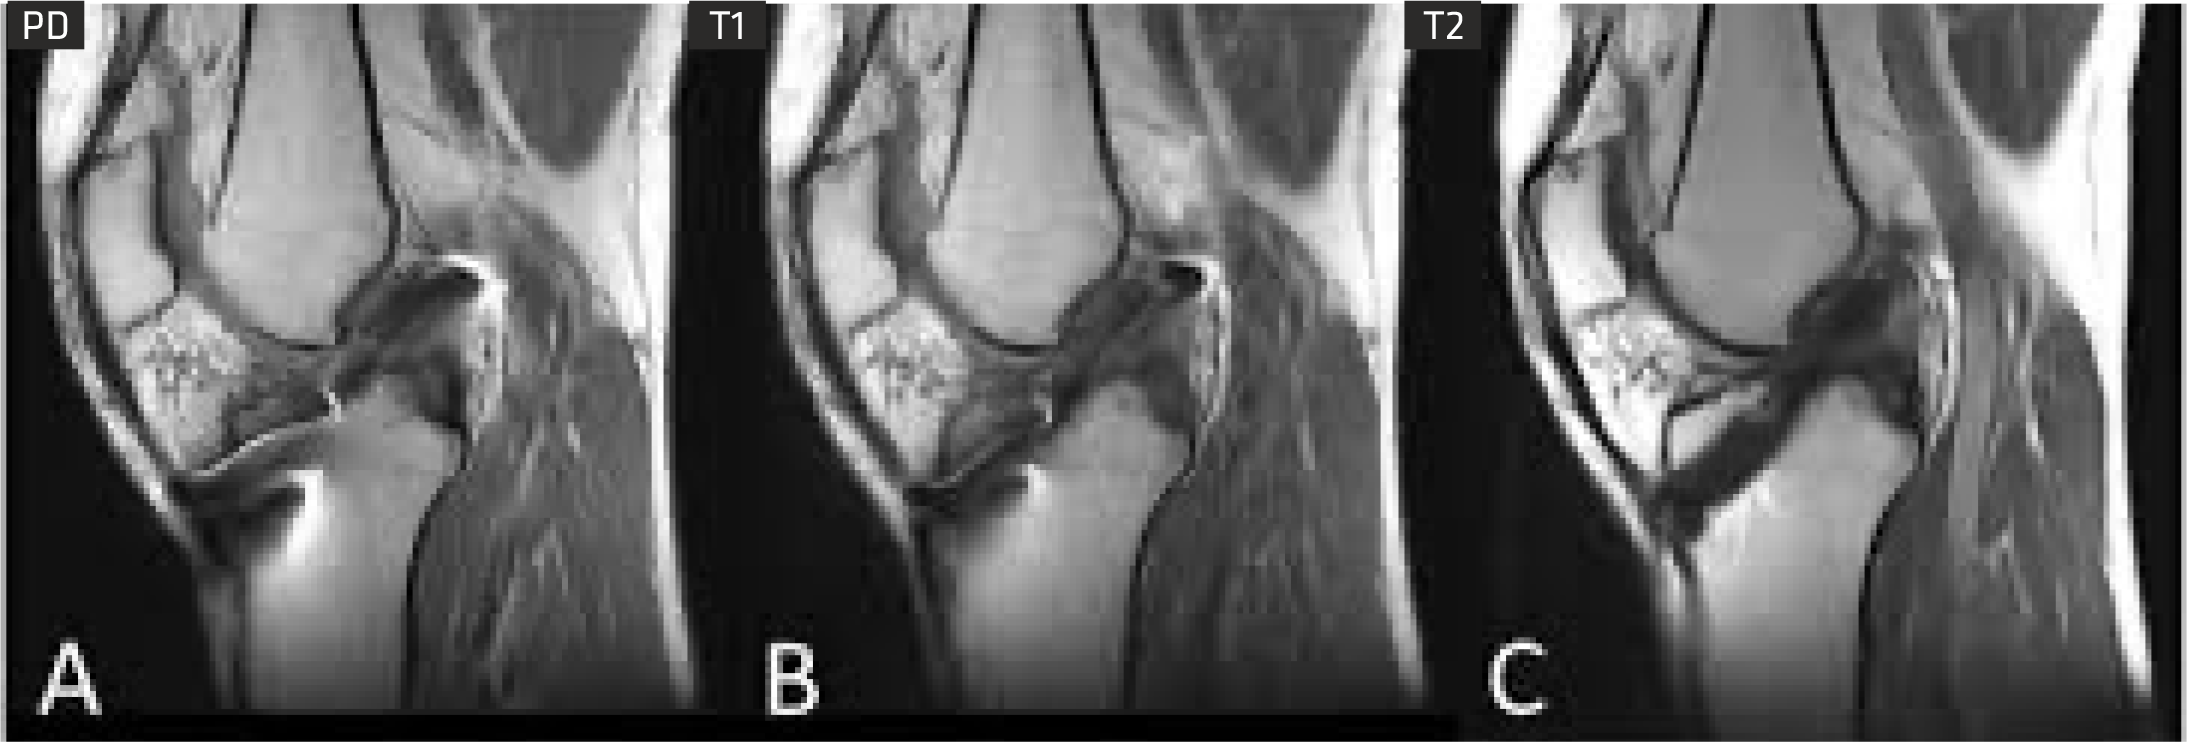

With advancements in MSK sequences, RF coils, computing technology and optimized magnet homogeneity, Clarity delivers high resolution musculoskeletal(MSK) images. This imaging technique enables you to image bone, joint and muscular soft tissue with remarkable tissue contrast.

Cartilage Quantification provides quantitative assessment of cartilage composition to track the degradation of tissues in the early stages of multiple pathologies? within joints, which can't be detected by conventional imaging techniques. It allows for non-invasive measurement of collagen content.

DIXON is a relatively new gradient-echo MR sequence that helps us visualize fat and water content in anatomical structures. It is reported to be useful in abdominal and brain imaging.